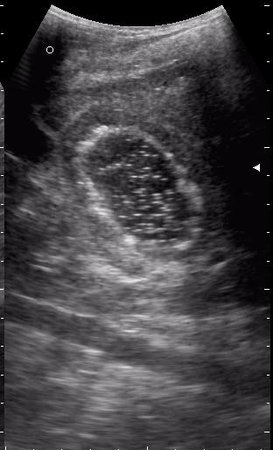

17-летняя девушка с множественными поражениями печени

абсцесс передней брюшной стенки (через 2 недели п.о.)

нагноение остаточной полости

спустя 8 мес. после операции